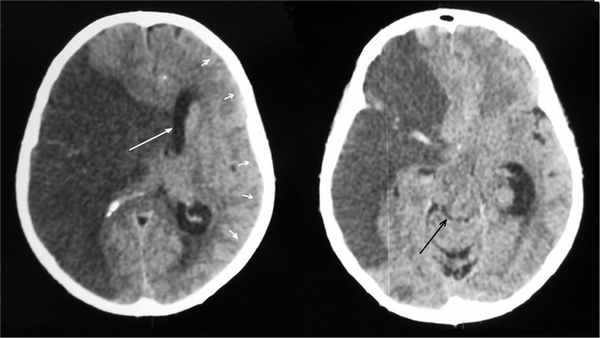

Отсроченное течение ДС отмечено у 15 пациентов. У всех больных не было поперечной дислокации головного мозга в первые 24 ч от начала заболевания, а при повторной КТ головного мозга на 2-е сутки поперечная дислокация была менее 7 мм (в среднем 5 мм, см. рис. 1). У 6 (40%) больных уровень бодрствования при госпитализации соответствовал ясному сознанию, у 9 (60%) — оглушению. У всех больных отмечено прогрессирующее снижение уровня бодрствования на 4-е сутки от начала заболевания, на 5-е сутки у всех развилось коматозное состояние (см. рис. 3). При проведении КТ на 5-е сутки отмечены поперечная дислокация (в среднем 18 мм), деформация охватывающей цистерны, соответствующая 2-й и 3-й степени по классификации В.Н. Корниенко, выраженный отек интактного полушария в виде сужения или сглаженности конвекситальных субарахноидальных пространств (рис. 4). Из 15 больных с отсроченным течением ДС были прооперированы 3, летальность у оперированных больных составила 67%, у неоперированных — 100%.

Рис. 4. КТ головного мозга больного 1-й группы с МИИ с отсроченным развитием ДС (5-е сутки от начала заболевания, угнетение уровня бодрствования до комы). Отмечаются смещение срединных структур влево на 16 мм (указано большой белой стрелкой), отек левого полушария в виде сужения конвекситальных субарахноидальных борозд (указано малыми белыми стрелками), видна деформация охватывающей цистерны 2-й степени по классификации В.Н. Корниенко (черная стрелка).